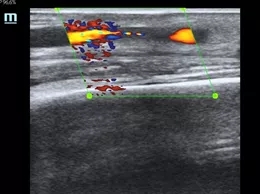

该患者为男性,规律血液透析,因内瘘流量不足,静脉压力高就诊,血管超声提示头静脉距离吻合口8-10cm处狭窄约70%,血流速度明显增快,节段性狭窄明确,符合球囊扩张成形术指征,同张愚主任讨论病情后,决定实施超声引导下经皮动静脉内瘘狭窄球囊扩张成形术。术后头静脉内径恢复正常,当日出院,第二日即应用内瘘进行血液透析,流量稳定,静脉压降至正常。

扩张前